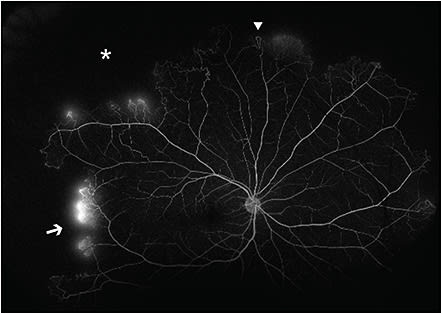

The Goldberg classification for PSR consists of 5 stages.12 Stage I PSR shows peripheral vascular occlusion, which can manifest as silver-wiring of the arterioles affected.16 The subsequent vascular remodeling at the border of perfused areas can lead to arteriovenous (AV) anastomoses, which are noted in stage II PSR. Stage III PSR consists of neovascular and fibrous proliferations. This includes the hallmark sea-fan neovascularization associated with sickle cell retinopathy (SCR). These are often found superotemporally at the border of perfused and nonperfused areas and are thought to arise from the venous component of AV anastomoses.12 Unlike AV anastomoses, sea-fan neovascularization demonstrates leakage on fluorescein angiography (Figure 1). Stage IV PSR is defined by the presence of vitreous hemorrhage caused by traction on neovascular fronds. Lastly, stage V PSR consists of tractional or combined rhegmatogenous and tractional retinal detachments. These are caused by vitreoretinal traction from neovascularization on ischemic retina, which is pathologically thin and thus more susceptible to retinal breaks. These detachments most commonly involve the ischemic temporal retinal periphery, a watershed zone for retinal vascular perfusion.12